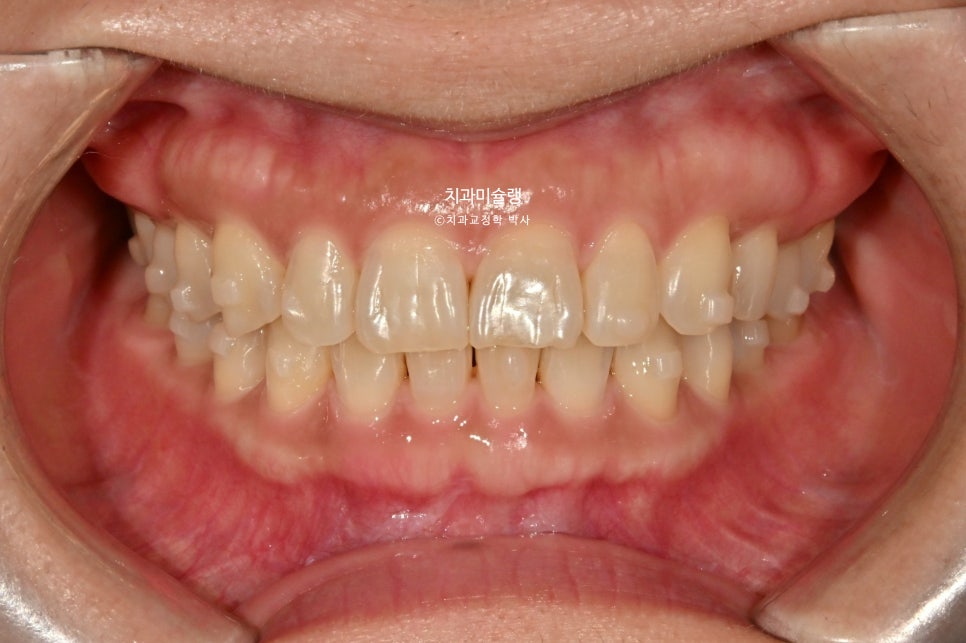

이제 전후비교 보겠습니다. 총 치료기간은 7개월, 재제작은 1회 했습니다.

치료 결과 비교

과개교합과 중심선은 개선되었으며

액간 뻗쳐있던 앞니 각도도 깔끔해졌습니다.

미소가 귀여우신 환자분. 깔끔해진 스마일라인이 돋보이네요.